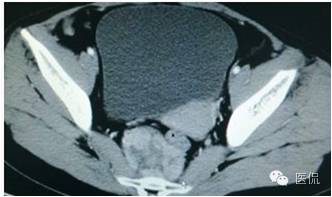

增强静脉期(CT值62HU)